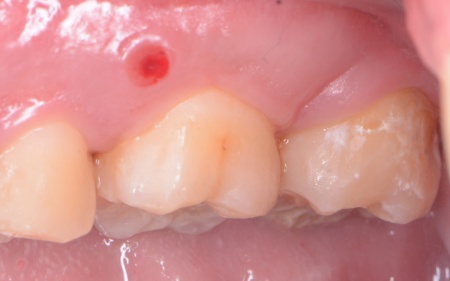

拝見したところ、左上奥歯(第2大臼歯)には被せ物が装着されていましたが、その下で虫歯が再発しており、歯の温存が難しい状態でした。

このまま放置すると、思うように噛めず食事がしにくかったり、周囲の歯に悪影響が及んだりするリスクがあります。

そのため、左上奥歯を抜いたうえで空いたスペースを補う治療を行い、しっかり噛めるようにする必要があると診断しました。